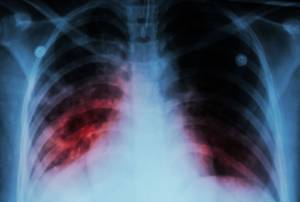

Локализация процесса вдоль корня легкого затрудняет рентгенологическую диагностику заболевания. Рентген в прямой проекции показывает расширение корня легкого, увеличение тени средостения, но дать более точные характеристики не представляется возможным. Более детальную информацию может дать компьютерная томография. Однако даже при качественном изображении остаются иногда вопросы.

Основным методом диагностики прикорневой пневмонии являются рентгенологические методы исследования. На рентгенограммах врач может увидеть локализацию воспаления, дифференцировать прикорневое воспаление лёгких от других заболеваний дыхательных путей. Но при прикорневой пневмонии интерпретация рентгенографического исследования может быть затруднительной. Затемнение от воспалённого очага часто наслаивается на корень лёгкого. В результате легочный корень на рентгеновском снимке «расширяется», что может указывать на новообразование или туберкулёз.